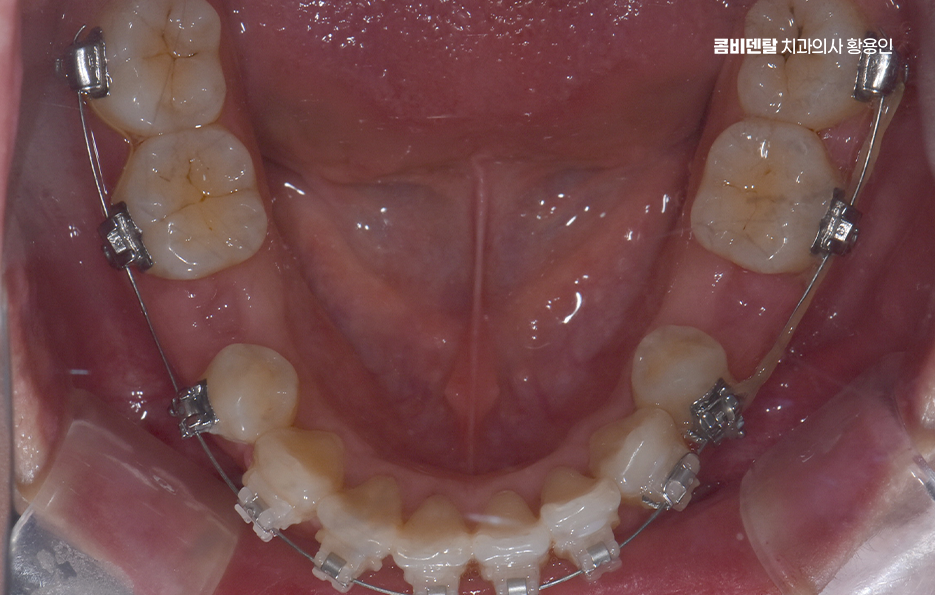

돌출입 팔자주름 교정 치아를 어떻게 움직이느냐에 따라 얼굴 인상이 달라지는 것인데 돌출입 교정은 일반적으로 소구치 네 개를 발치한 후, 앞니를 뒤쪽으로 밀어넣고 악궁을 재배열하는 방식으로 진행되며 앞니가 뒤로 이동하고 자연스럽게 입술이 들어가게 되고, 입술 돌출도가 줄어들면서 얼굴이 전반적으로 부드럽고 조화로운 느낌으로 바뀔 수 있어요

옆모습에서 입이 덜 나와 보이고, 턱선이 또렷해지는 것도 이런 원리에서 비롯되며 치아 배열 자체는 물론이고, 입술과 턱 근육의 균형이 맞춰지기 때문에 얼굴 인상이 부드럽고 안정적으로 바뀌는 거예요.

돌출입 팔자주름 교정 그럼 팔자주름은 어떻게 변하느냐는 질문도 많은데 돌출입이 있는 사람들은 입 주변 근육에 지속적으로 긴장이 들어가기 때문에 팔자주름이 더 도드라져 보이는 경우가 많고 입술이 앞으로 나와 있다 보니, 코 밑에서부터 입꼬리로 이어지는 주름이 더 깊게 파이고, 표정이 굳어 보일 수도 있었어요.

그런데 치아를 뒤로 이동시키면서 입술이 안쪽으로 정리되면, 입 주변의 긴장도 줄어들게 되고, 자연스럽게 팔자주름이 완화되는 효과가 생기는 것이며 물론 주름 자체를 없애는 시술처럼 극적인 효과는 아니지만, 돌출이 줄어들면서 팔자주름이 덜 도드라져 보이고 얼굴의 입체감이 개선되는 건 분명한 변화라고 볼 수 있어요